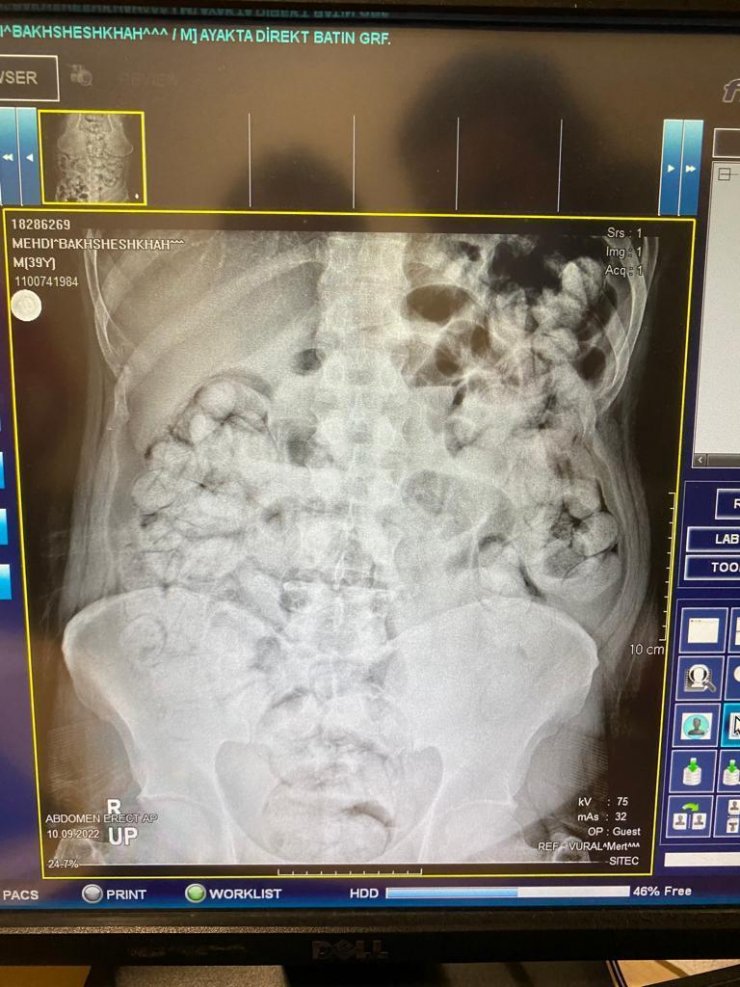

Erzurum- Erzincan kara yolunda uygulama yapan İl Emniyet Müdürlüğü Narkotik Suçlarla Mücadele Şube Müdürlüğü ekipleri, 10 Eylül'de İran plakalı bir otobüsü durdurdu. Yolculardan Mehdi B., Milad F. ve Siraus G.'nin hareketlerinden şüphelenen polis, onları röntgen çekimi için hastaneye götürdü. Yapılan muayene ve röntgen çekimi sonrası şüphelilerin uyuşturucuları kapsül haline getirerek yuttukları belirlendi. Yapılan çalışmayla şüphelilerin midesindeki toplam 210 kapsül içindeki 3 kilo 192 gram Afyon sakızı ve 62 kapsül halinde 709 gram eroin çıkarıldı. Emniyetteki işlemlerinin ardından adliyeye sevk edilen 3 şüpheli 14 Eylül günü tutuklandı.